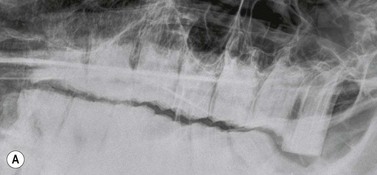

Fig. 13.20 (A) Intra-oral radiograph of a maxillary cheek teeth row.

Radiograph courtesy of J. Easley.

image

(B) Intra-oral radiograph taken intra-operatively during a dental extraction procedure. A small bone-opacity fragment can be seen in the rostral aspect of the alveolus (arrow).

(Radiograph courtesy of W.H. Tremaine.)